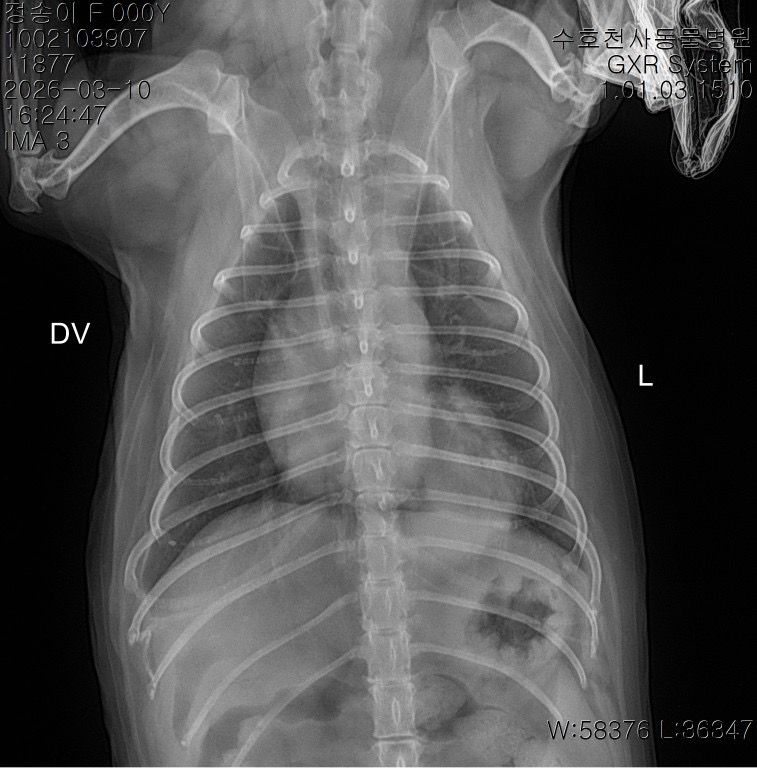

말씀주신 것처럼 보여주신 방사선에서 흉강 내 종양 (폐, 흉강 등)이 의심되는 상황입니다. 다만 방사선 사진만으로는 종양 여부와 정확한 위치, 개수, 성격을 완전히 판단하기 어렵고 CT 촬영을 통해 정확한 판단이 이루어져야 수술 여부 등을 결정할 수 있습니다. 좌측 폐는 앞엽과 뒷엽으로 나눠지긴 하고, 사진 상으로는 좌측 뒷엽 혹은 오른쪽 폐와 왼쪽 폐 사이에 있는 덧엽 부분에도 종괴가 위치하는 것으로 보이지만, 방사선으로는 어느 폐엽에서 발생한 것인지 정확히 구분할 수는 없습니다.

종괴가 단일 병변인지 여러 개인지, 정확히 어느 폐엽에서 시작되었는지, 주변 조직이나 다른 폐엽으로 이어져 있는지,

원발성 종양인지 전이성 병변인지 등을 알려면 CT 촬영이 필요하며 치료 방향도 CT 결과에 따라 달라집니다. 만약 한 두개의 폐엽에 국한된 단일 종괴라면 경우에 따라 해당 폐엽을 제거하는 수술을 고려하는 경우가 있습니다. 하지만 주변 조직으로의 침습, 원격전이 혹은 너무 많은 엽을 포함하고 있어 수술 후 호흡 합병증이 예상되는 경우 수술로 완치 기대는 어렵습니다. 빠른 CT 촬영을 추천드립니다.

사진상으로는 상당히 전형적인 원발성 폐종양의 방사선 양상이지만 말씀 하신 "방사선 엑스레이 촬영 한 것을 통해서서도

폐 종양인지 아닌지, 갯수를 확인가능한지

한 폐엽에만 있는 상황인건지 아니면 윗쪽 중간 폐엽과도 이어져있는지 원발성,악성 등등"에 해당하는 내용은 방사선 사진으로 평가하는게 아닌 흉부 CT검사로 확인해야 하는 사항들입니다. 흉부 방사선 검사는 저렴하지만 정확도와 세밀한 내용 평가에 제한이 있습니다. 우선 주치의와 상의하시고 흉부 CT검사를 촬영 한 후에 침습이나 전이 여부 평가하고 수술 계획 잡으시기 바랍니다. 원발성 폐종양인 경우 악성이더라도 수술로도 완치가 가능한 몇 안되는 질환이니 수술을 빨리 하면 할 수록 좋을 수 있으니 아이에게 주워진 시간을 아끼시기 바랍니다.